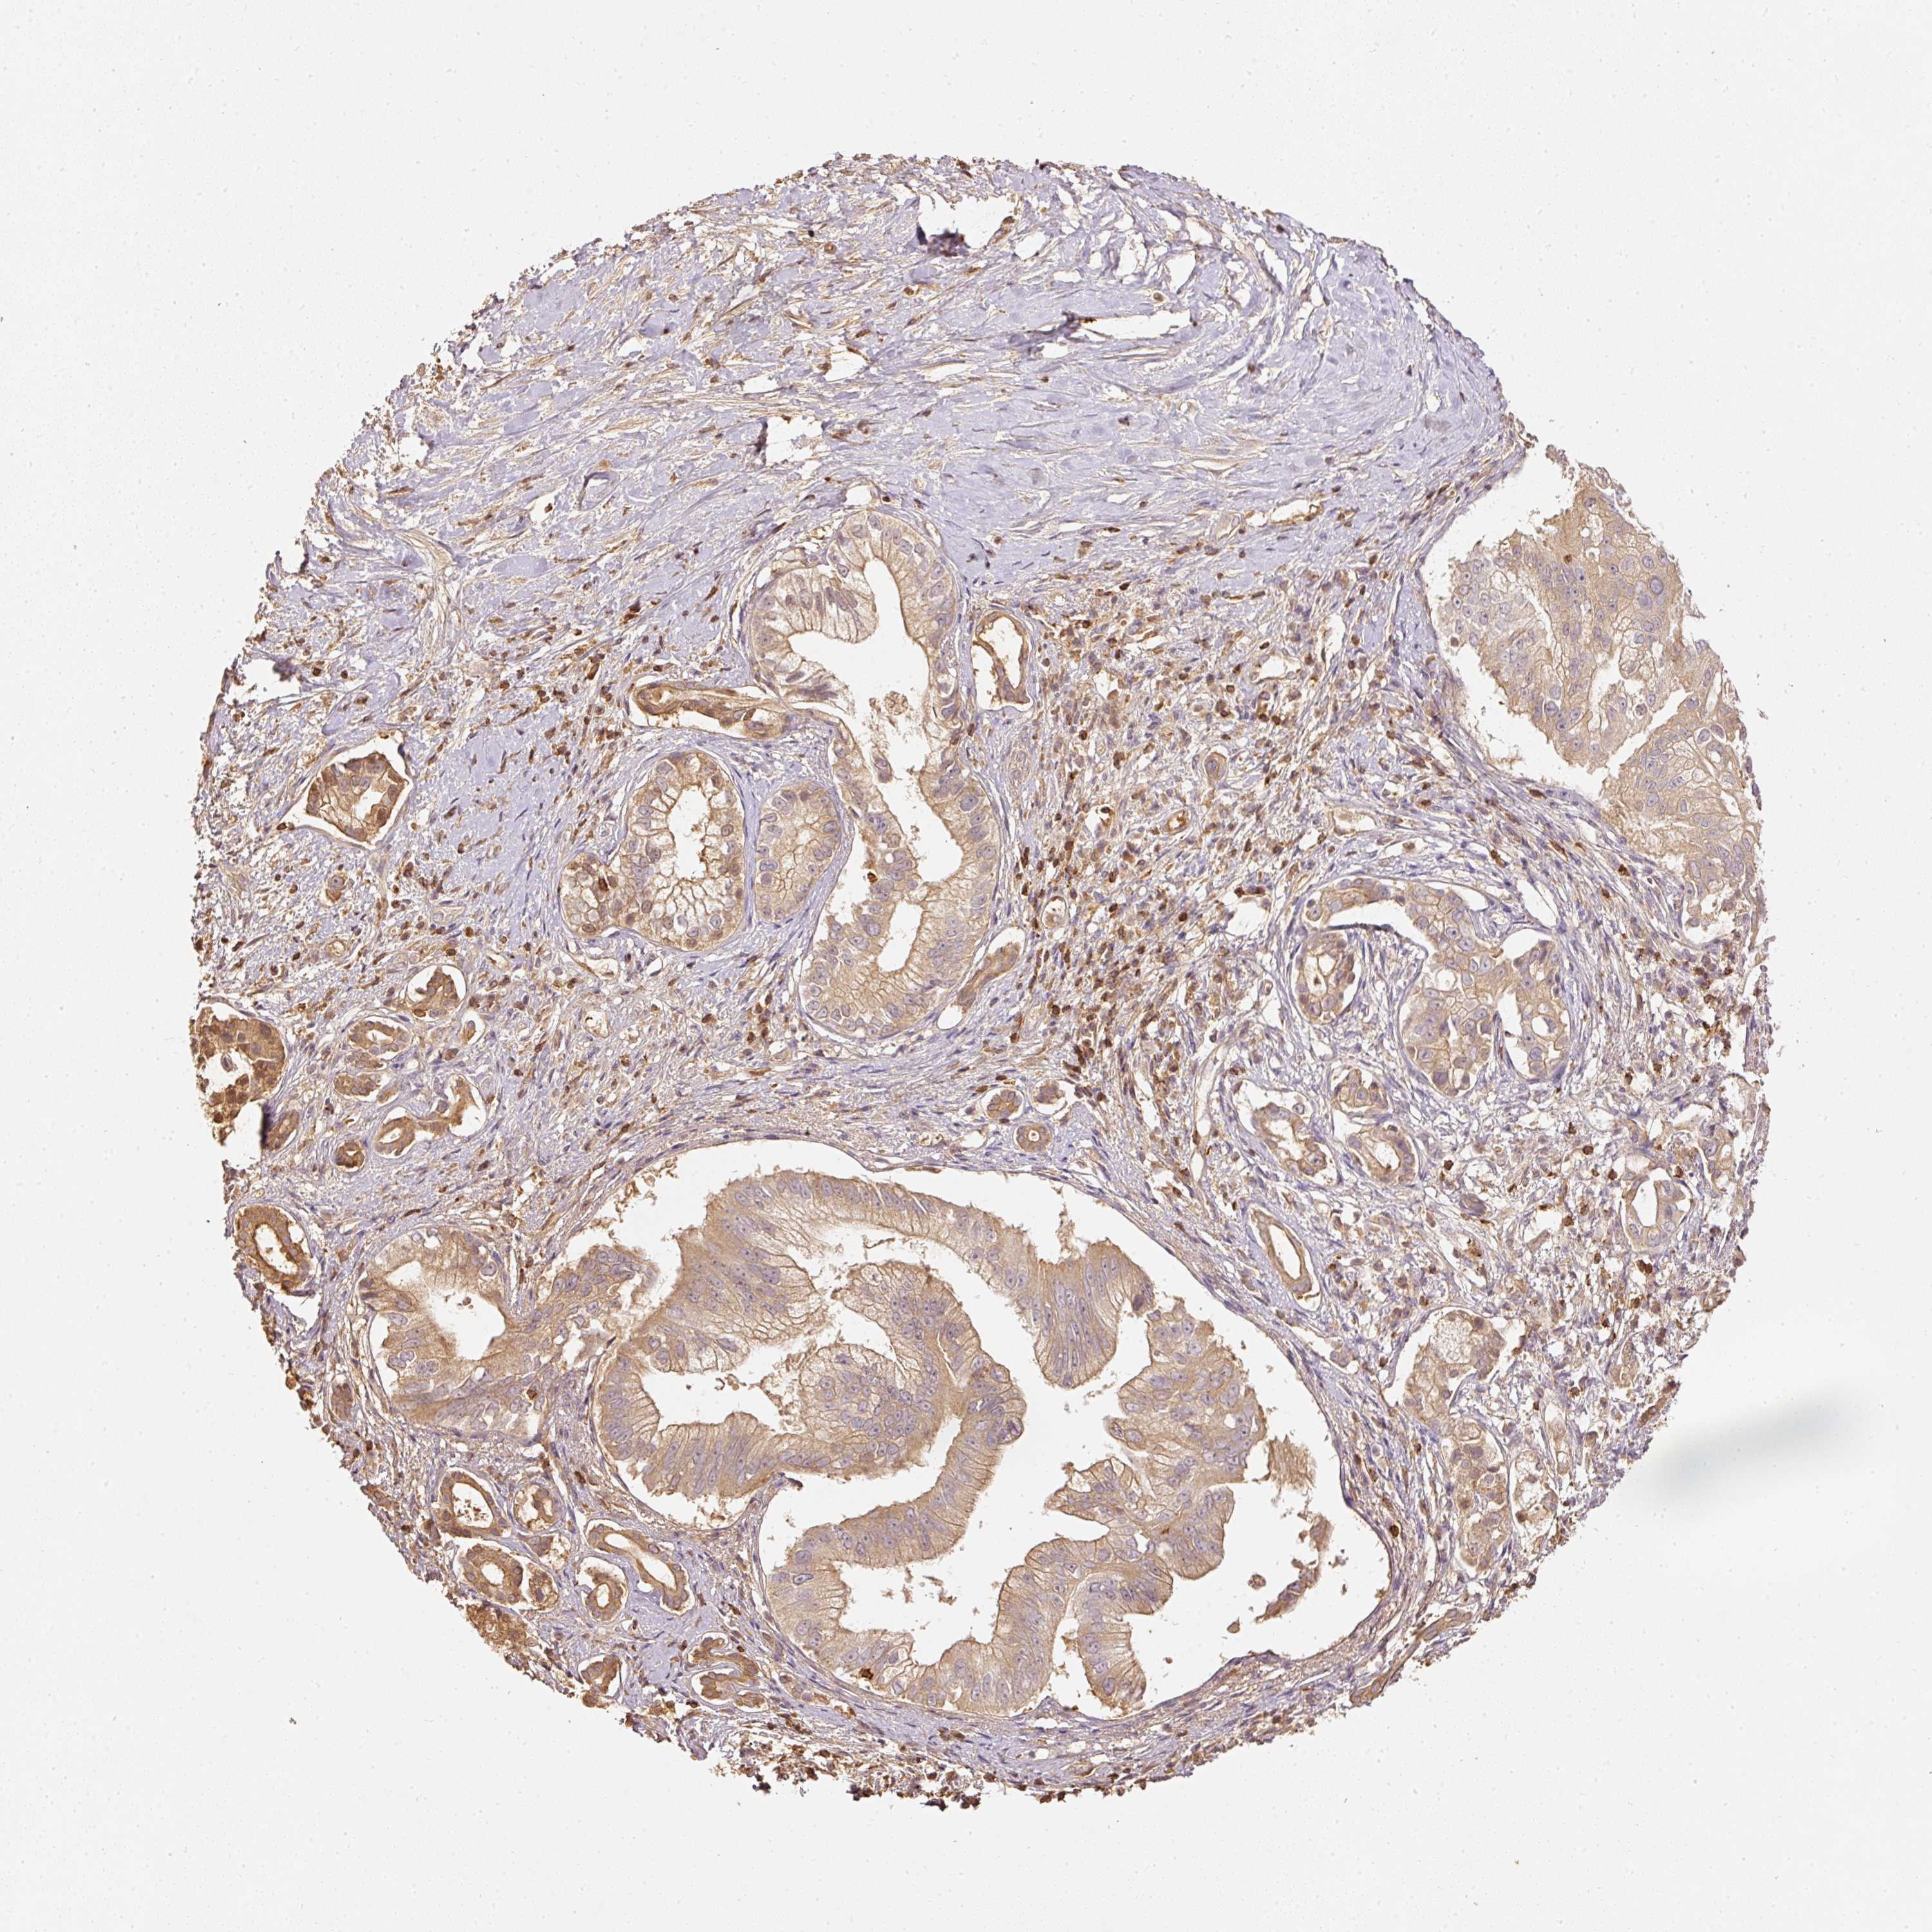

PANCREATIC CANCER - Protein expressioni

A mouse-over function shows sample information and annotation data. Click on an image to view it in a full screen mode. Samples can be filtered based on level of antibody staining by selecting one or several of the following categories: high, medium, low and not detected. The assay and annotation is described here.

Note that samples used for immunohistochemistry by the Human Protein Atlas do not correspond to samples in the TCGA dataset.

Antibody stainingi

Antibody staining in the annotated cell types in the current human tissue is reported as not detected, low, medium, or high, based on conventional immunohistochemistry profiling in selected tissues. This score is based on the combination of the staining intensity and fraction of stained cells.

Each image is clickable and will lead to virtual microscopy that enables deeper exploration of all samples and also displays staining intensity scores, fraction scores and subcellular localization as well as patient and tissue information for each sample.

Antibody HPA018849

Antibody HPA019536

Antibody CAB033987

Staining

High

Medium

Low

Not detected

Intensity

Strong

Moderate

Weak

Negative

Quantity

>75%

75%-25%

<25%

None

Location

Nuclear

Cytoplasmic/membranous

Cytoplasmic/membranous,nuclear

Adenocarcinoma, NOS